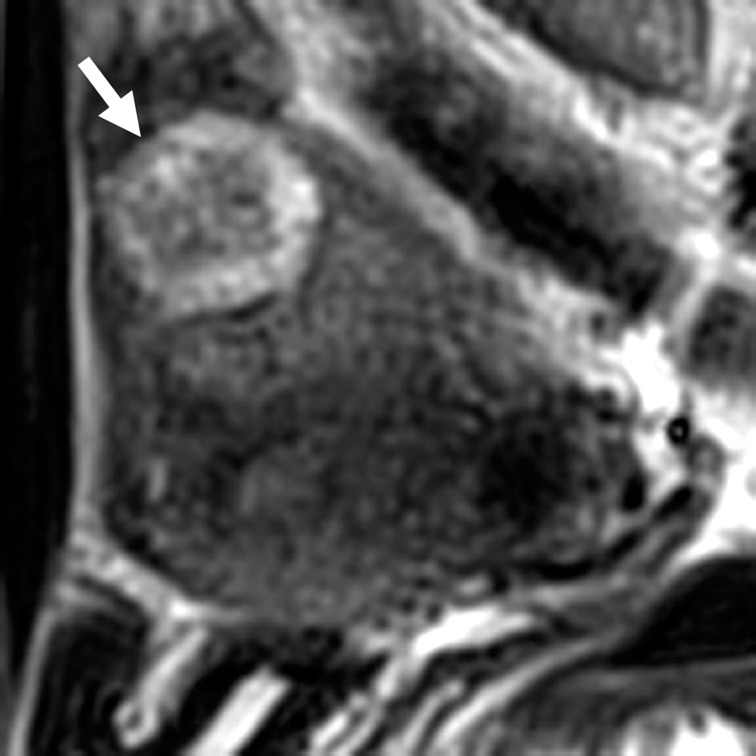

Fig. 5.

A 43-year-old woman with uterine adenomatoid tumor (lesion 9). A solid tumor of 28 mm in size located in the outer myometrium was revealed on sagittal T2-weighted image. The tumor showed target-like appearance: peripheral ring-like high-intensity area (arrow) and central low-intensity area.